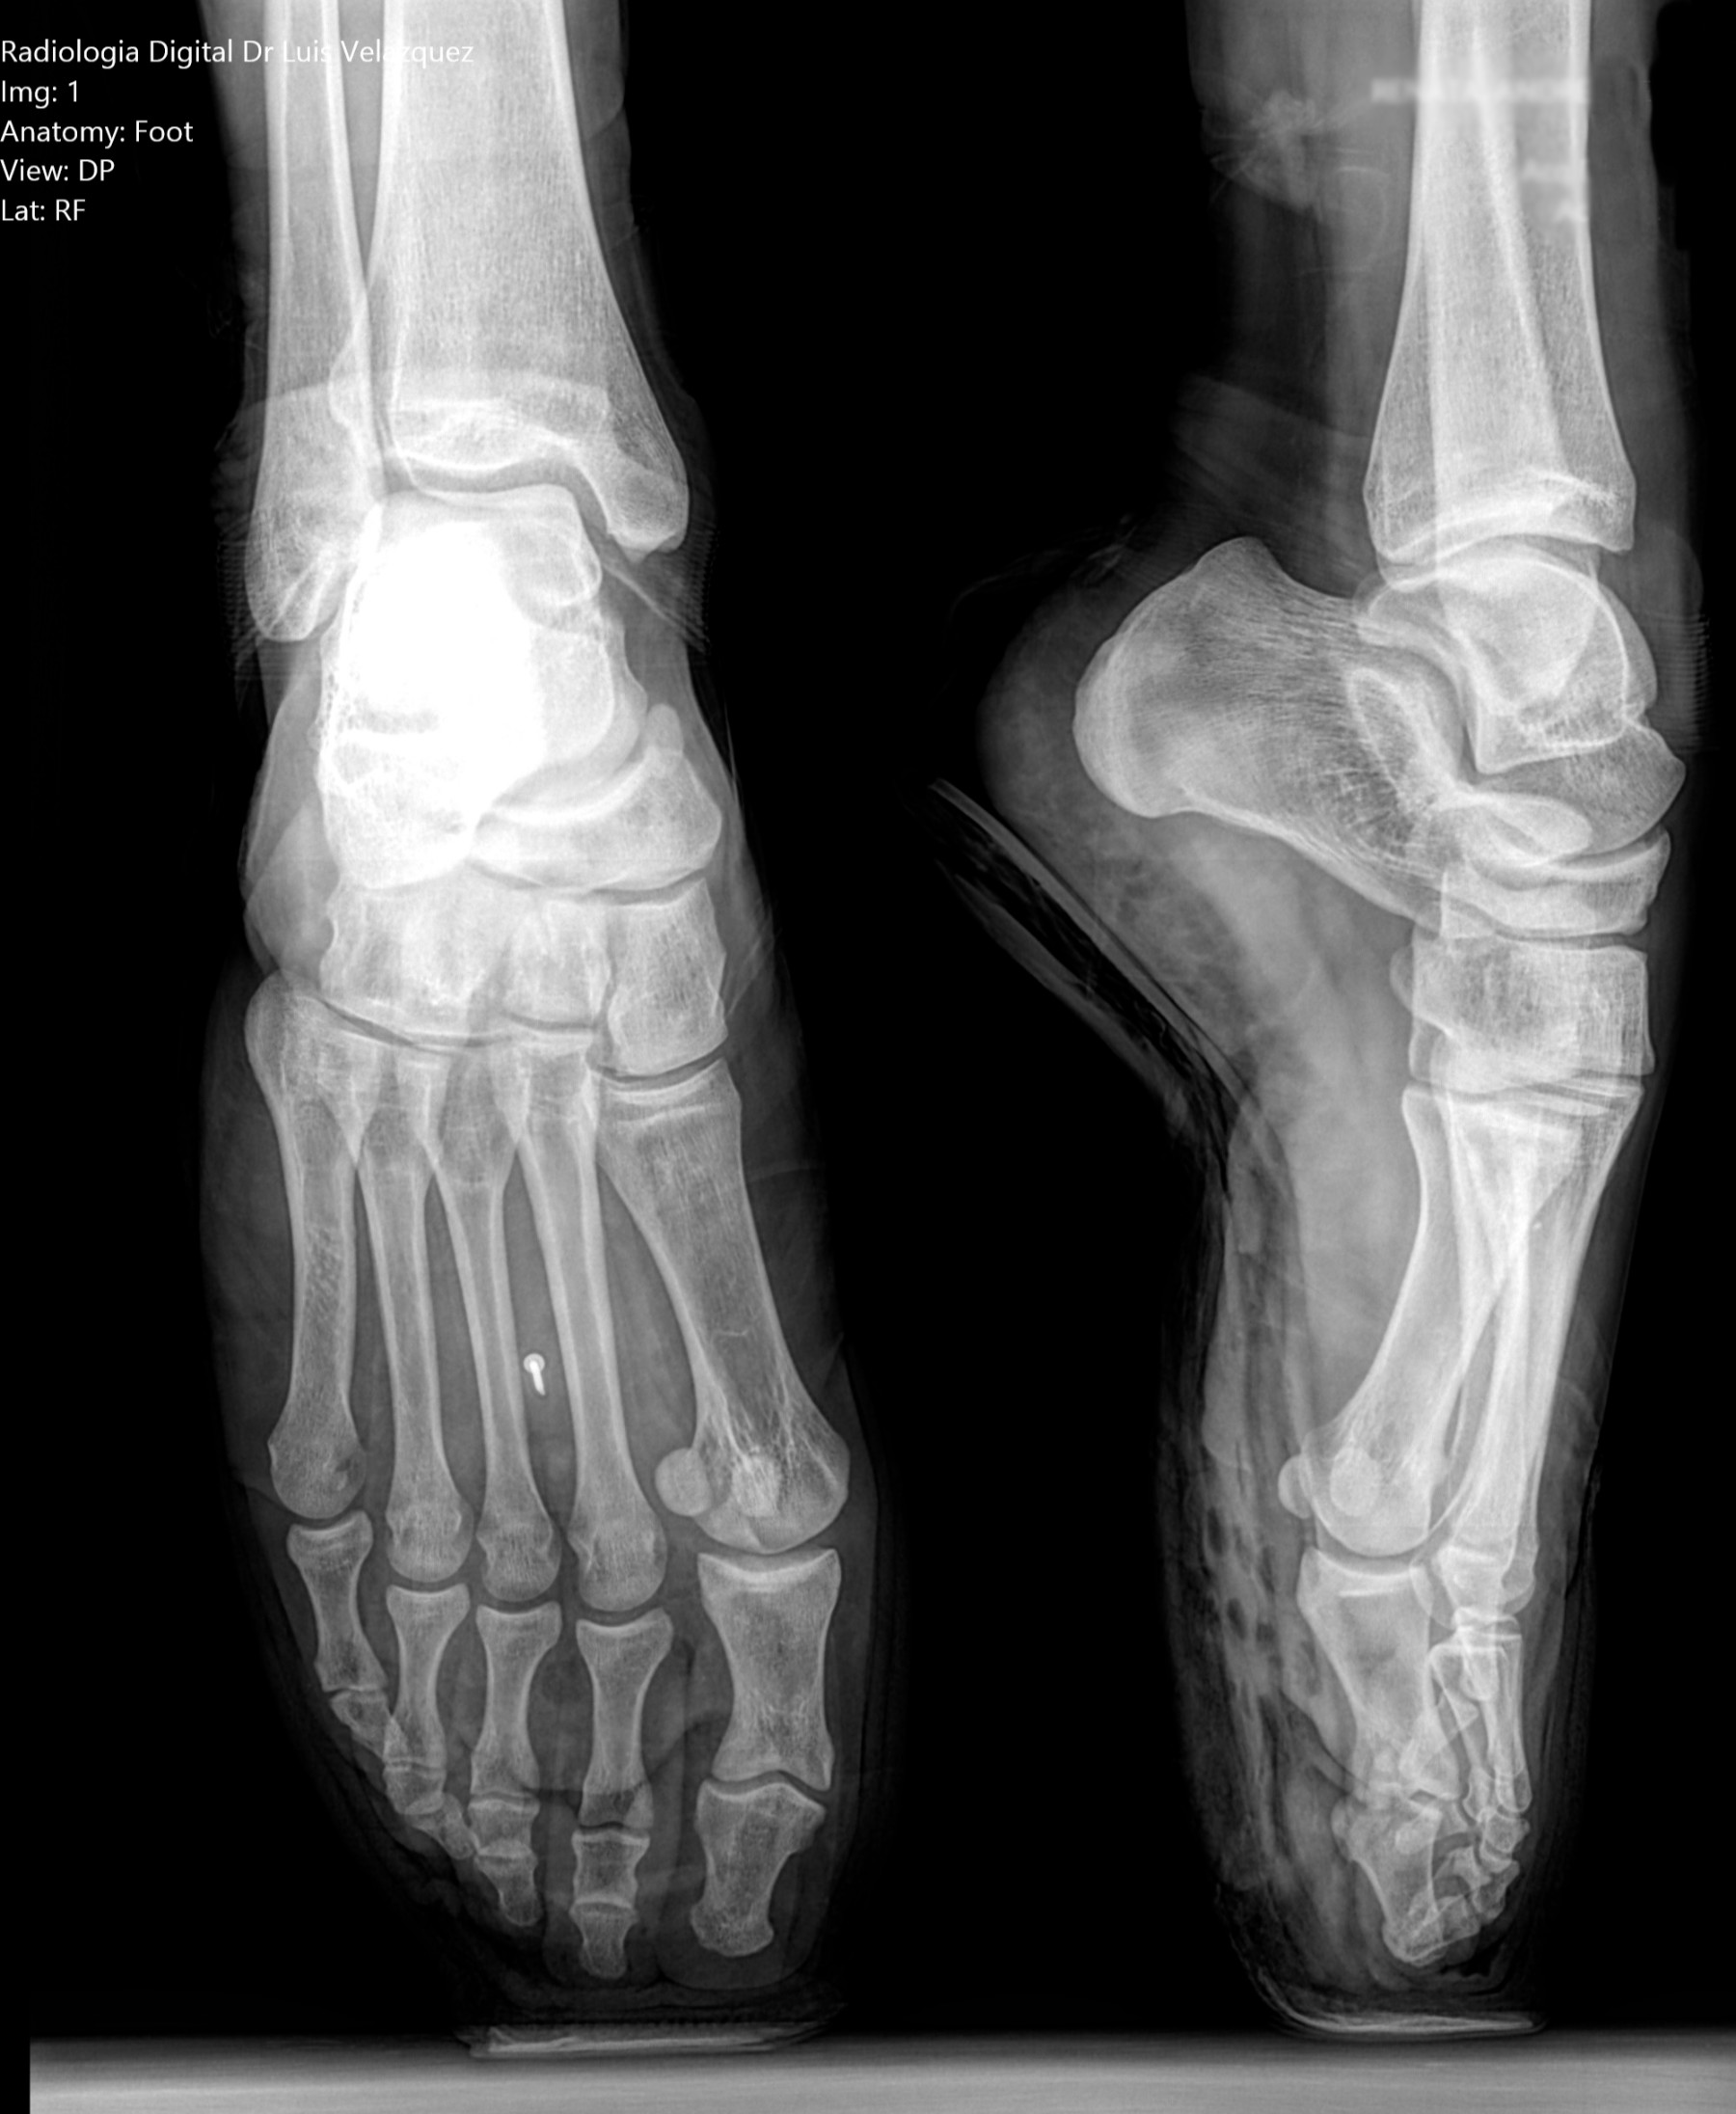

Cambios Térmicos en las Extremidades de Caballos,

Asociados a Golpes y su Evaluación por Termografía.

Los caballos de salto, en competencia, pueden derribar obstáculos y lastimarse. Si se golpean, no siempre claudican. Considerando al calor como un signo de inflamación, se evaluaron los cambios térmicos de 6 áreas de las extremidades torácicas y pelvianas de 23 caballos de salto en nivel de competencia de 1.05 a 1.60 m de altura, por medio de termografía durante 4 días de competencia (N=2208 áreas).